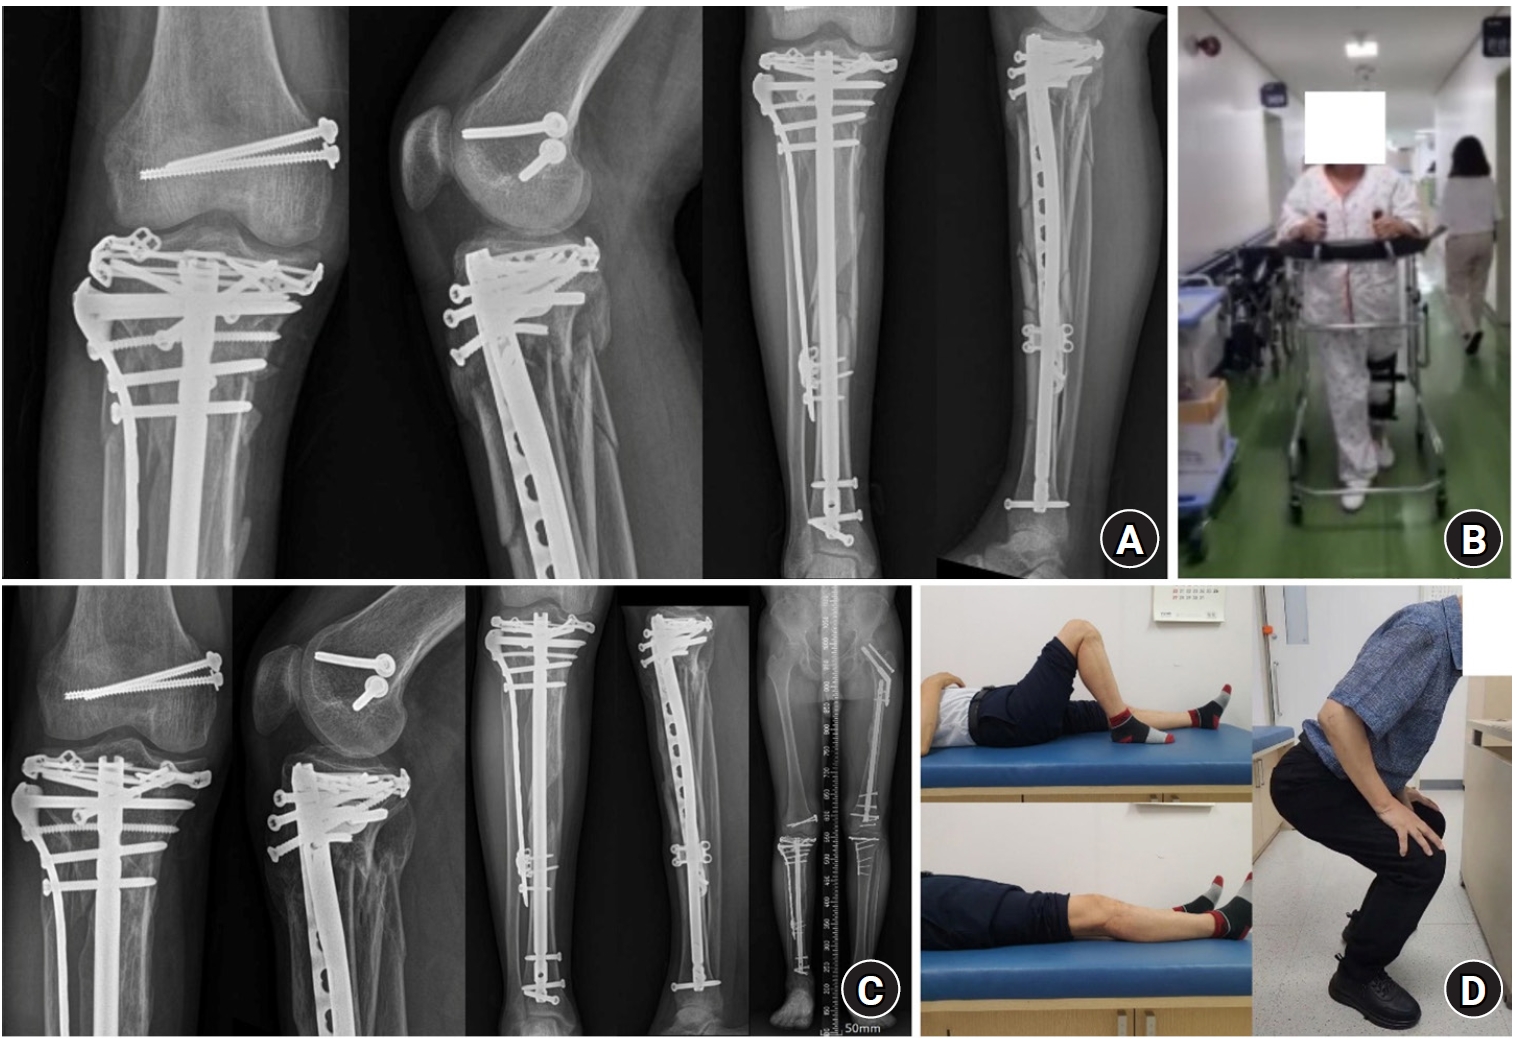

Fig. 8.

Follow-up plain radiographs and clinical photographs taken 6 weeks and 1 year 6 months after surgery. (A) Plain radiographs 6 weeks postoperatively. (B) Clinical photograph showing the patient walking independently 6 weeks after surgery. (C) Plain radiographs 1 year 6 months postoperatively. (D) Clinical photographs 1 year 6 months after surgery showing good knee range-of-motion and the ability to perform squatting exercises.

Fig. 8. Follow-up plain radiographs and clinical photographs taken 6 weeks and 1 year 6 months after surgery. (A) Plain radiographs 6 weeks postoperatively. (B) Clinical photograph showing the patient walking independently 6 weeks after surgery. (C) Plain radiographs 1 year 6 months postoperatively. (D) Clinical photographs 1 year 6 months after surgery showing good knee range-of-motion and the ability to perform squatting exercises.

One week later, the left distal radius and ulna and concomitant ipsilateral forearm both-bone fractures were surgically treated, which concluded the surgical procedures. Passive knee range-of-motion exercises were initiated immediately after surgery. Weight bearing and walking ambulation began approximately 4 weeks after surgery, following transfer from the intensive care unit to the general ward. Six weeks after surgery, the patient could walk independently (Fig. 8A and 8B), and bone union was achieved at 6 months. At 9 months, the patient underwent reconstruction of the posterior cruciate ligament to address right knee instability and was subsequently able to return to full physical activity (Fig. 8C and 8D).